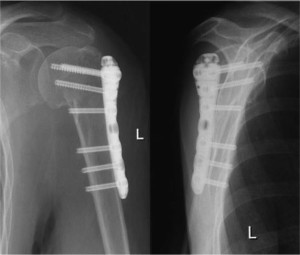

Для восстановления положения костных отломков используют специальные костные фиксаторы. Чаще всего используется тракция по оси конечности, для этого могут привлекаться помощники или специальные механические устройства для растяжения. После восстановления правильного положения отломков осуществляется их фиксация с помощью металлических конструкций.

Если у вас есть открытая позиция, то можно использовать металлический фиксатор для фиксации.

Преимущество открытого совмещения заключается в его открытости. В отличие от альтернативного метода, здесь можно использовать металлический фиксатор.

Этот метод известен как остеосинтез. Для его проведения могут применяться различные инструменты, такие как винты, шпицы и другие.

Аппарат Илизарова заслужил хорошую репутацию благодаря своей уникальной конструкции, включающей четыре кольца наружной фиксации, удерживаемые на спицах, пронизывающих костные обломки. Одной из особенностей этого аппарата является возможность удлинения кости до четырнадцати сантиметров. Кроме того, после применения аппарата пациент может сразу начать двигать конечностью и даже ступать на травмированную ногу.

Разумеется, у каждого способа лечения есть свои недостатки. При использовании остеосинтеза металлический материал проникает непосредственно в кость, что может привести к возникновению инфекции и развитию остеомиелита. Тем не менее, преимущества этого метода намного значительнее, особенно учитывая их большее количество. Среди них:

- надежное закрепление;

- пациент способен ходить через три дня после проведения операции;

- фиксация переломов костей сохраняется в течение тридцати дней, пока не наступит полное сращивание, что позволяет пациенту вести обычный образ жизни.